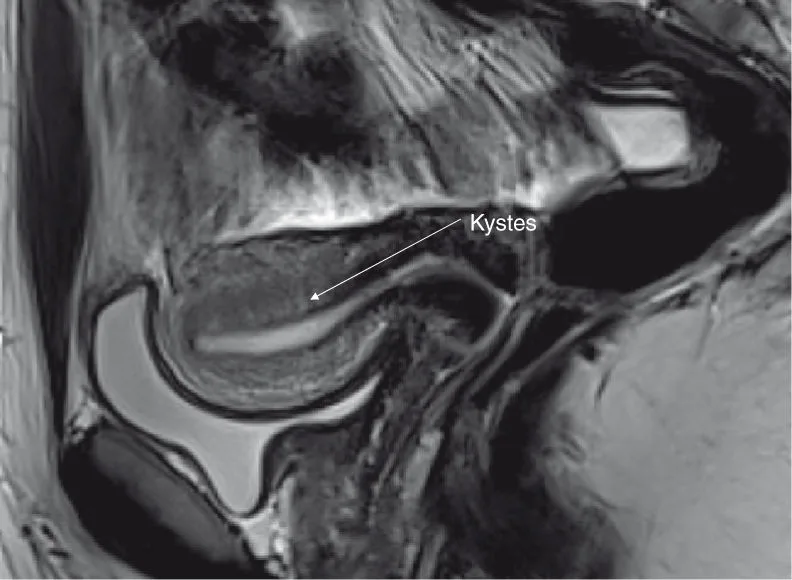

directs : irrégularités des berges de l'endomètre, microkystes en hypersignal T2, prédominant dans les zones de fragilité endomyométriale maximale, soit en postérieur sur la ligne médiane à hauteur du fond de l'endomètre et en regard des cornes endométriales (figures 6.1 et 6.2) ;

Figure 6.1. Endométriose utérine interne. • 15 ans, vierge. • Dysménorrhée avec AS ; EVA : 8. • Ménorragies • J 18, cycle spontané. Source : Dr Petit.